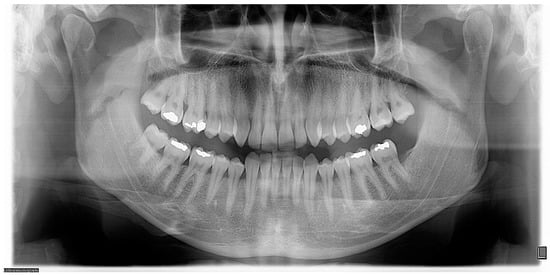

5. The Importance of Head Orientation

6.1. Symmetry